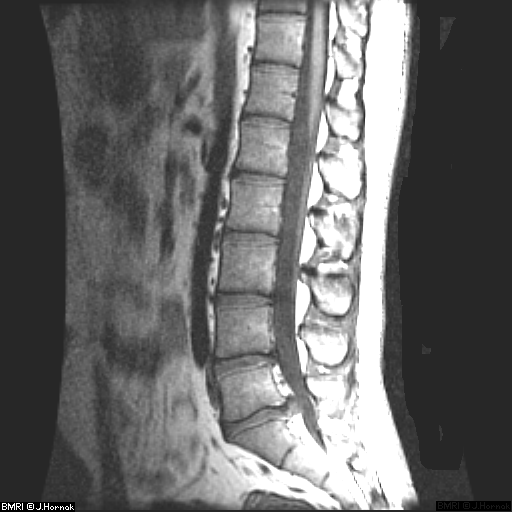

- Позвоночник